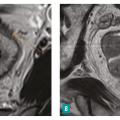

Les paramètres d’extension locale sont :

– la distance entre le pôle inférieur de la tumeur et la marge anale et/ou le bord supérieur du sphincter interne (fig. 3 ) ;

– la morphologie, la dimension de la tumeur et sa localisation sur un cadrant horaire ;

– la présence ou non d’arguments en faveur d’une histologie mucineuse, de plus mauvais pronostic (tumeur en hypersignal T2)4 [fig. 4 ] ;

L’atteinte du mésorectum et du péritoine est caractérisée par :

– la marge circonférentielle (CRM) : distance la plus courte en millimètres entre le bord externe de la tumeur ou d’une adénopathie, d’un nodule tumoral, d’un embole vasculaire extramural et le fascia recti, ainsi que sa localisation horaire (fig. 3 ) ;

– pour les tumeurs haut situées : un éventuel envahissement de la ligne de réflexion péritonéale par la tumeur.

L’atteinte ganglionnaire (stade N), les dépôts tumoraux au sein du mésorectum, la présence ou l’absence d’invasion vasculaire extramurale (facteur pronostique péjoratif indépendant5) et d’éventuelles métastases, notamment les ganglions extrarégionaux (fig. 5 ), doivent également être mentionnés.

– Concernant le stade T, le stade T3 peut être divisé en quatre sous-stades en fonction de l’extension au sein du mésorectum : T3a, inférieure à 1 mm ; T3b, de 1 à 5 mm ; T3c, de 5 à 15 mm ; T3d supérieure à 15 mm. Cette distinction intervient dans le choix du traitement selon les dernières recommandations européennes.2

– Concernant l’extension ganglionnaire, un petit axe supérieur à 8 mm est hautement prédictif d’une invasion tumorale. Cependant, la taille de plus de la moitié des ganglions atteints est inférieure à 5 mm.6 Le critère de taille isolé est donc insuffisant pour évaluer l’envahissement tumoral7, 8 ; des critères morphologiques prédictifs de malignité doivent également être pris en compte (tableau 2 ).